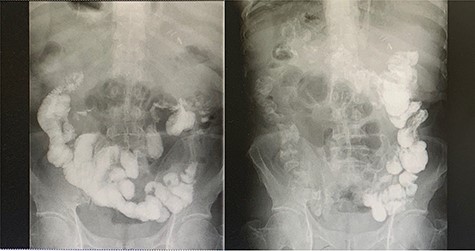

A 52-year-old male had no obvious inducement of epigastric pain for >3 months presenting persistent stabbing pain, accompanied by back pressure, fatigue, loss of appetite and hiccup. He went to a local hospital for treatment because of aggravated abdominal pain. Gastroscopy showed: (i) gastric polyps and (ii) chronic atrophic gastritis. The symptoms were not relieved after oral medication. Two weeks later he had jaundice with clay-like stool, so he went to the local hospital and underwent a color Doppler ultrasound examination. The results showed that: (i) visceral inversion; (ii) solid space-occupying at the head of the pancreas; (iii) dilated inner diameter of the intrahepatic and extrahepatic bile ducts and main pancreatic duct; (iv) fatty liver and (v) enlarged gallbladder volume and wall rough. The patient was admitted to our hospital complaining of ‘epigastric pain >3 months ago, jaundice with clay-like stool for 1 week’. The patient had no significant medical, surgical or drug history. Physical examinations were unremarkable except for a weight loss of ~20 kg since the onset of the disease. Blood and laboratory tests were carried out, and they showed elevated values of liver enzymes, with a clear elevation in the values of Enzyme gamma-glutamyl transferase (GGT) and alkaline phosphatase (ALP), as well as tumor markers CA19-9, CEA and CA72-4, which are indicative of the presence of an obstructive lesion (Table 1). After preoperative examinations, he was diagnosed with pancreatic cancer. His CT scan (Fig. 1) showed: (i) mirror dextrocardia; total visceral inversion; (ii) pancreatic space-occupying lesions; (iii) intrahepatic and extrahepatic bile duct dilation; (iv) intrahepatic calcification and (v) multiple small cysts in the left kidney, and the MRI scan has confirmed the previous results (Fig. 2). A perioperative plan has been made for a LPD. The patient was put under general anesthesia in a supine split–leg position. The laparoscopic instruments were connected (Fig. 3). Diagnostic laparoscopy confirmed a mirror transportation of organs hence confirming SIT, considering the preoperative assessments and intraoperative exploration, a LPD, and intestinal adhesiolysis was performed. Major vessels along with thoracic and abdominal organs were transposed as mirror images of the normal anatomy, a 17-cm paramedian incision in the upper left abdomen was made to accomplish the resection of the organs which includes the distal stomach—the duodenum, the upper segment of the jejunum, the common bile duct and the gallbladder. According to conventional loop reconstruction, the reconstruction of the alimentary tract was performed. Three drainage tubes were placed at the sites of the anastomoses. Although there were anatomical variations, the operation went smoothly. The blood pressure of the patient was stable and the anesthesia effect was satisfactory within 150-ml intraoperative blood loss. The postoperative specimens were sent to the pathological lab. Postoperative fluoroscopy was normal (Fig. 4). The patient had a total hospital stay of 26 days; 15 days postoperative hospital stay, and was discharged without any complications.

Preoperative contrast-enhanced CT confirming SIT with space-occupying at the head of pancreas and duodenum.